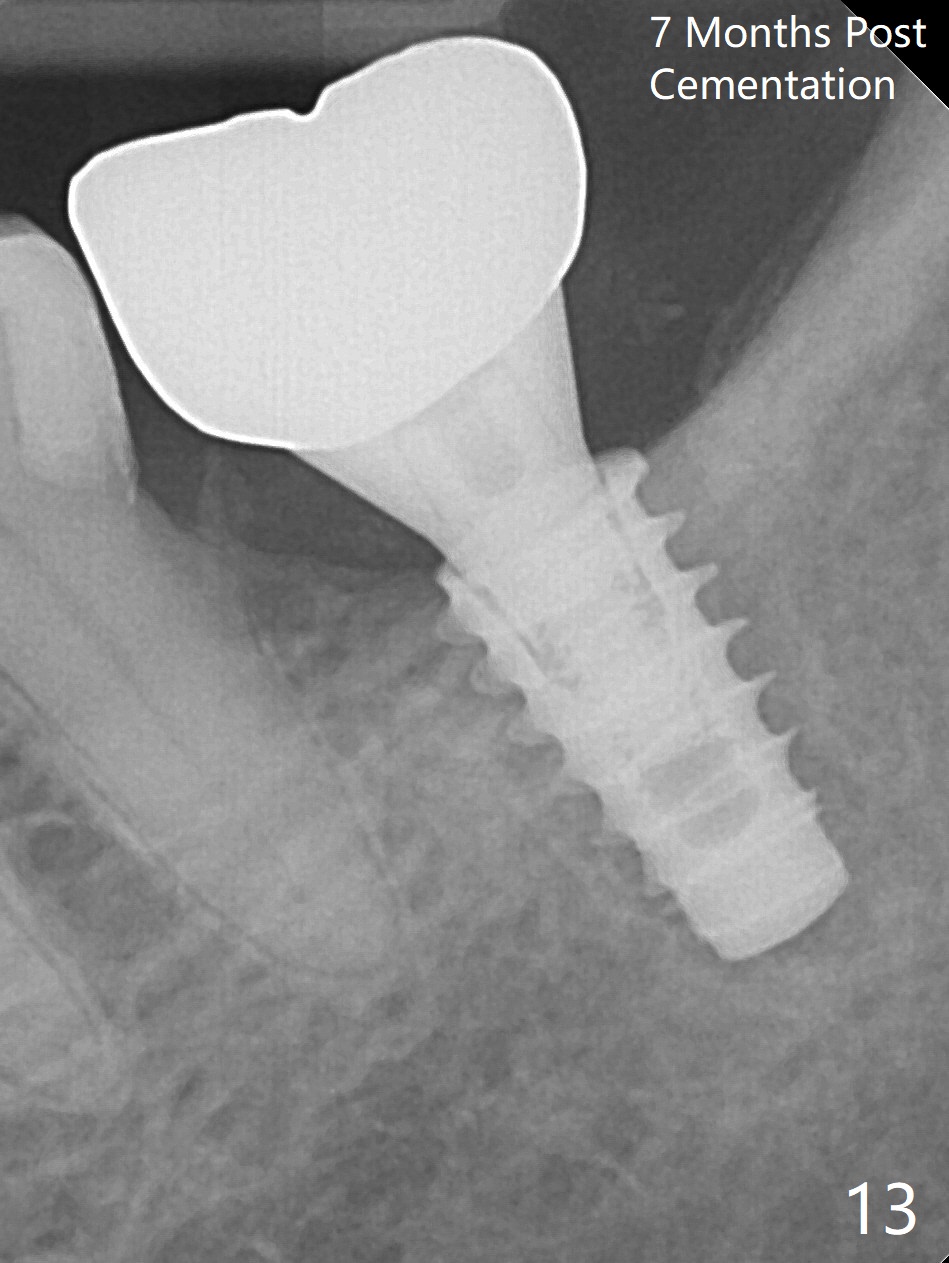

There is no apparent bone loss 4 months postop (Fig.10). There is chewing pain in spite of occlusal adjustment 7 months post cementation (Fig.11-13: increased radiolucency around the implant). The crown/abutment is removed and a healing abutment is placed (6x3 mm); the implant is stable. The patient return for re-evaluation in 3 months (15 months postop); radiolucency appears to reduce (Fig.14). But there is pain when the healing abutment is being removed. After local anesthesia, the implant is removed with a wrench. Following debridement of the osteototomy (intact, although tender), a 5x10 mm dummy implant with SLA surface is placed (Fig.15). After 5.5 mm tap, a 5.5x8.5 mm implant is placed with >50 Ncm (Fig.16). A 6.8x5 mm healing abutment is placed, followed by periodontal dressing. Re-analysis of preop CBCT shows that the bone density at the site is low: 70 units average. Progressive loading is necessary for this case 4-6 months postop. The soft and hard tissues around the implant seem to heal 4 months postop (Fig.17).